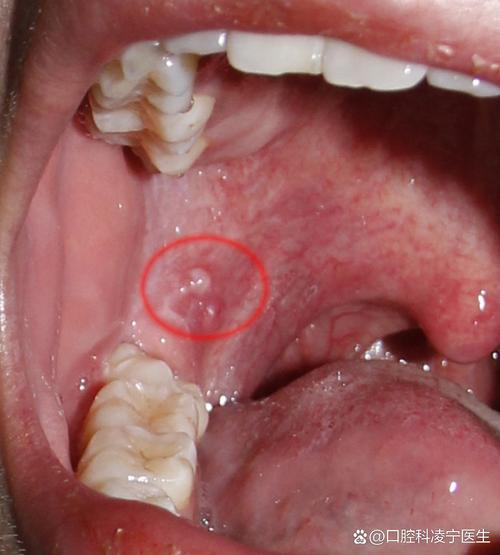

口腔左侧内壁肉疙瘩是何问题?

口腔鳞状细胞乳头状瘤

(图片来源网络,侵删)- 特点:一种良性的肿瘤,通常呈带蒂的、菜花样的疣状物,表面可能有些粗糙,但通常无痛。